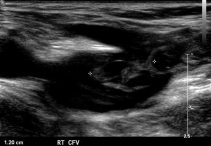

As in many other vascular conditions, venous insufficiency is diagnosed by combining the history, physical examination and proper imaging studies. The history and physical examination actually result in the signs and symptoms that can be found above. As for imaging – the most common imaging study used for the diagnosis of venous insufficiency is duplex ultrasound. Duplex ultrasound achieves both the diagnosis of reflux and its extent, and may also assist in understanding the cause – such as showing a deep vein thrombosis. Other non-invasive tests that may be used in order to differentiate between venous and arterial disease include ankle brachial index and pulse volume recording.